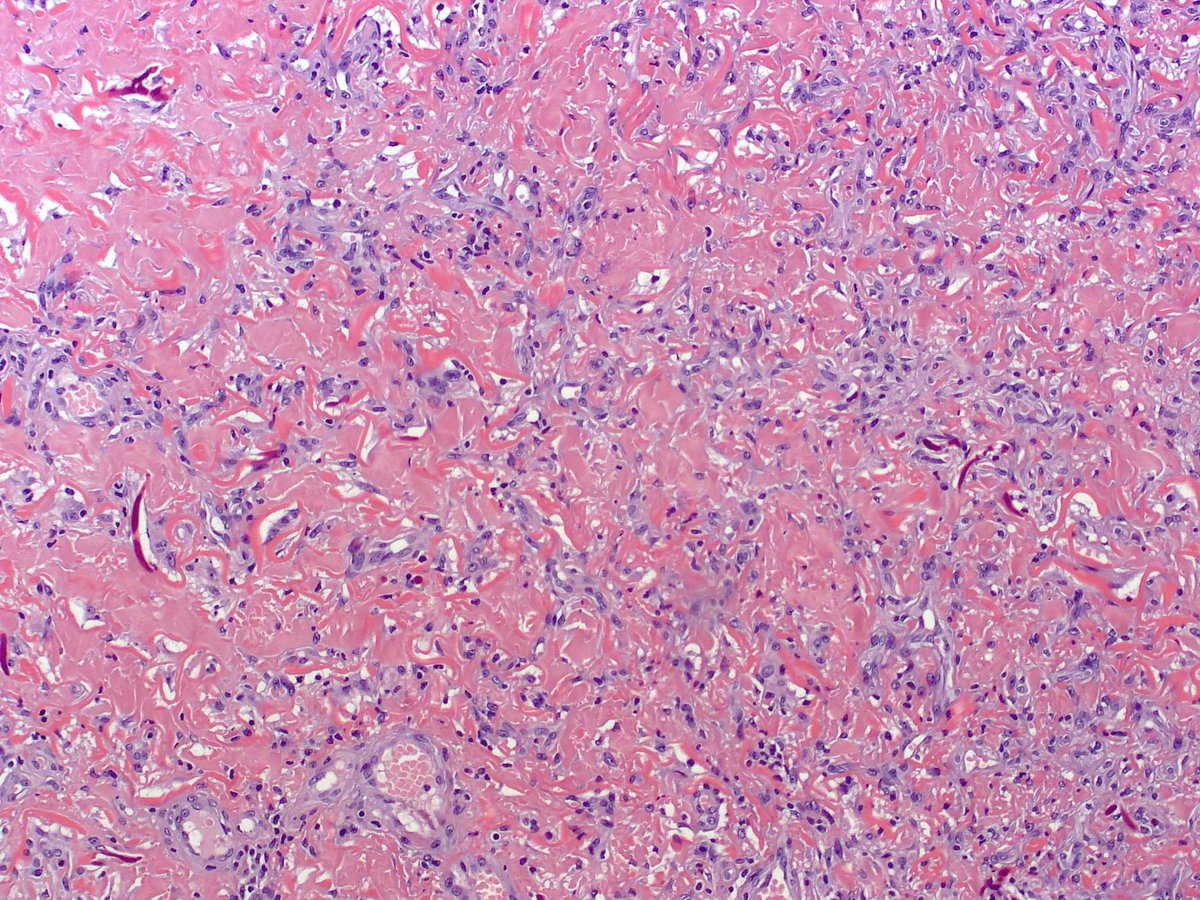

Lump on the scalp.  Easy if you use your brain, a bit tricky for those of us who only think skin deep....#dermpath #dermatology #pathology

And the answer is ... cutaneous meningioma. Quite uncommon, and easy to start thinking adnexal, melanocytic, cellular neurothekeoma if your practice stops at the fascia like me! All you need to know in: pubmed.ncbi.nlm.nih.gov/22288971/ #dermpath #pathology #dermatology